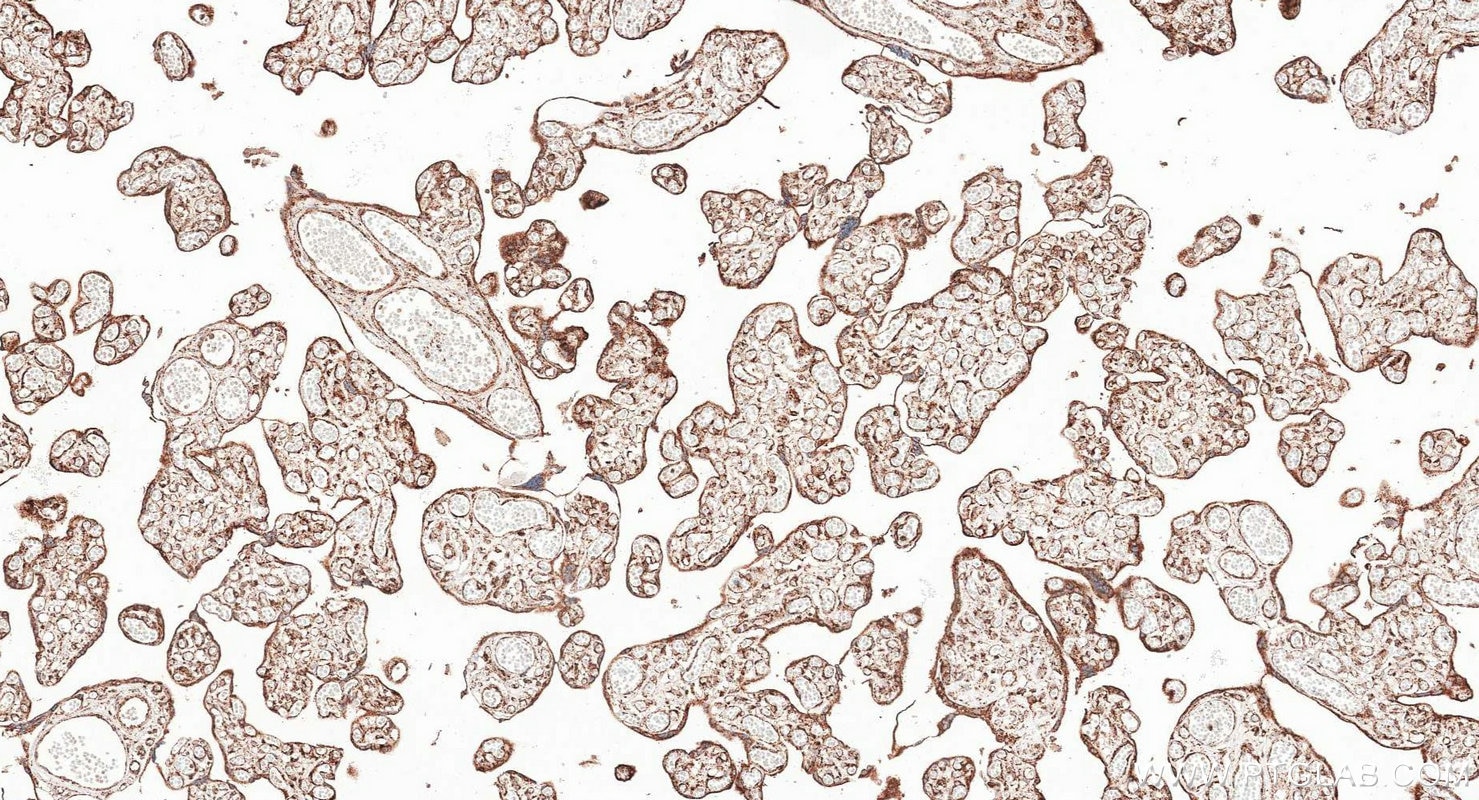

| Positive IHC detected in | mouse liver tissue, human placenta tissue, mouse brain tissue Note: suggested antigen retrieval with TE buffer pH 9.0; (*) Alternatively, antigen retrieval may be performed with citrate buffer pH 6.0 |

| Immunohistochemistry (IHC) | IHC : 1:500-1:2000 |